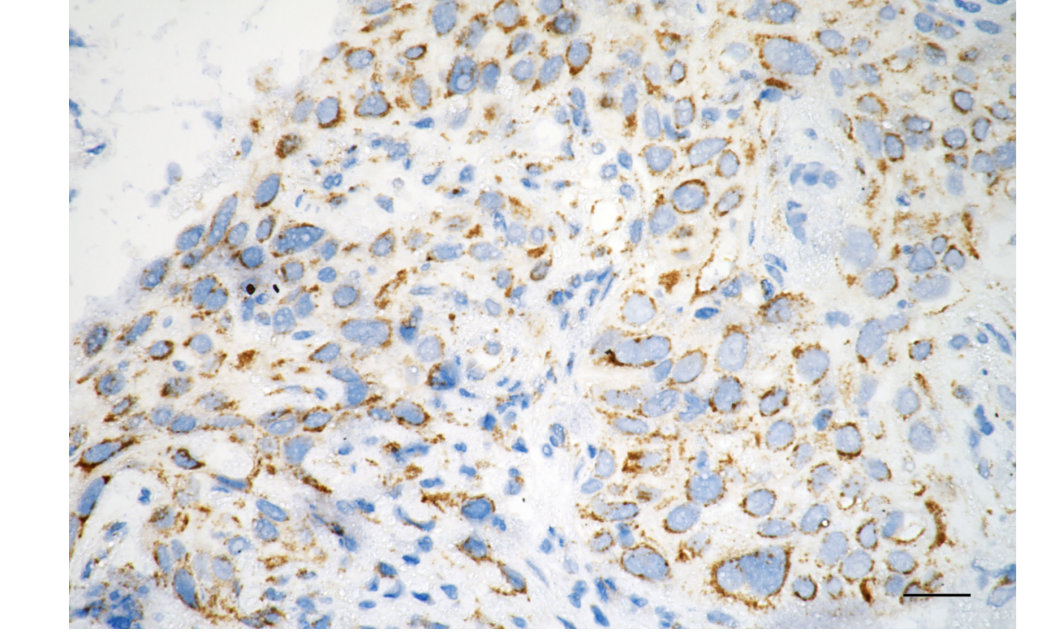

• Immunohistochemistry was performed on paraffin-embedded human esophageal carcinoma using caspase 8 antibody. Antigen retrieval was done in sodium citrate buffer (pH 6.0). DAB was used for detection, with hematoxylin counterstaining. Images were acquired using a Nikon Ci-L Plus microscope (40× objective). Scale bar: 25 μm.